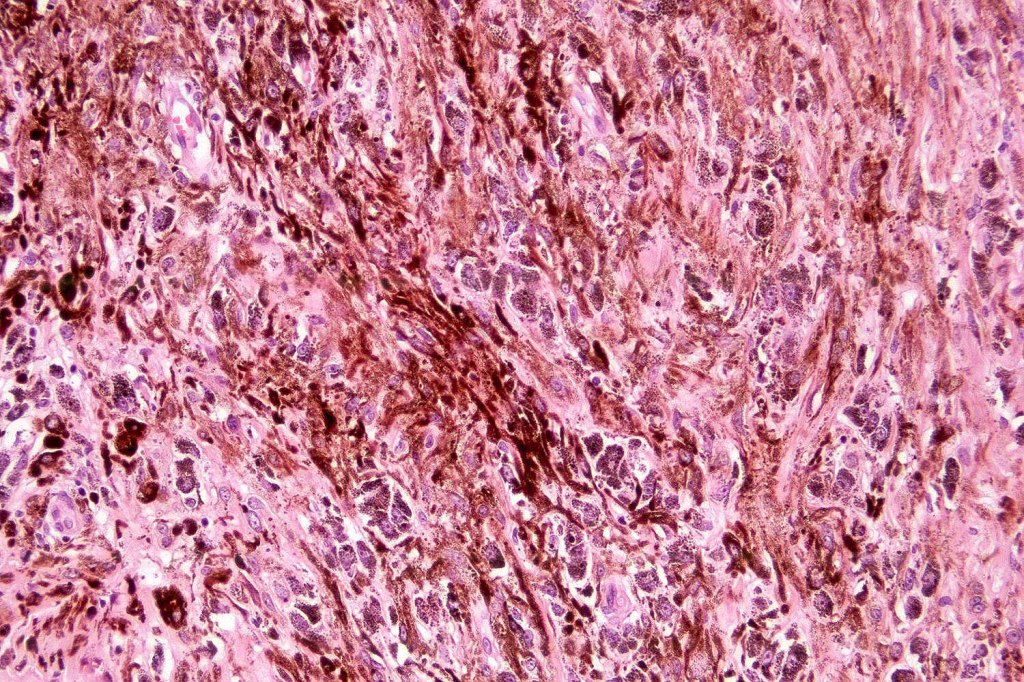

Atpical blue nevus

This is exceedingly rare and the diagnosis should be used very sparingly. It is likely quite benign although very occasionally, a sentinel node biopsy is positive. Great care must be taken to make sure that a blue nevus-like melanoma isn’t missed. It shows the low power features of a blue nevus but high power scrutiny reaveals pleomorphism, nuclear hyperchromatism and increased mitotic activiy (<1 sq mm). Abnormal mitoses are absent as is necrosis. Perineural involvement can be seen but lymphovascular invasion is absent.